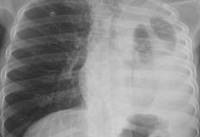

Эмпиема плевры - скопление гнойного экссудата в полости плевры с вторичной компрессией лёгочной ткани при плеврите.

Острая эмпиема плевры. Кашель с выделением мокроты. Длительные и частые приступы кашля с отделением большого количества мокроты свидетельствуют о наличии бронхоплеврального свища. Боль в грудной клетке минимально выражена при спокойном дыхании, резко усиливается во время полного глубокого вдоха. Одышка. Нарушение голосового дрожания или отчётливая эгофония. Тупой или притуплённый перкуторный звук на стороне поражения, верхняя граница тупости соответствует линии Эллиса-Дамуазо-Соколова. Ослабление или отсутствие дыхания при аускультации над областью выпота. Бронхиальное дыхание над прилежащим к выпоту сдавленным лёгким. Покраснение кожи возникает только при прорыве гноя из полости эмпиемы под кожу. Общее состояние прогрессивно ухудшается: слабость, потеря аппетита, похудание, гектическая температура тела, частый пульс.